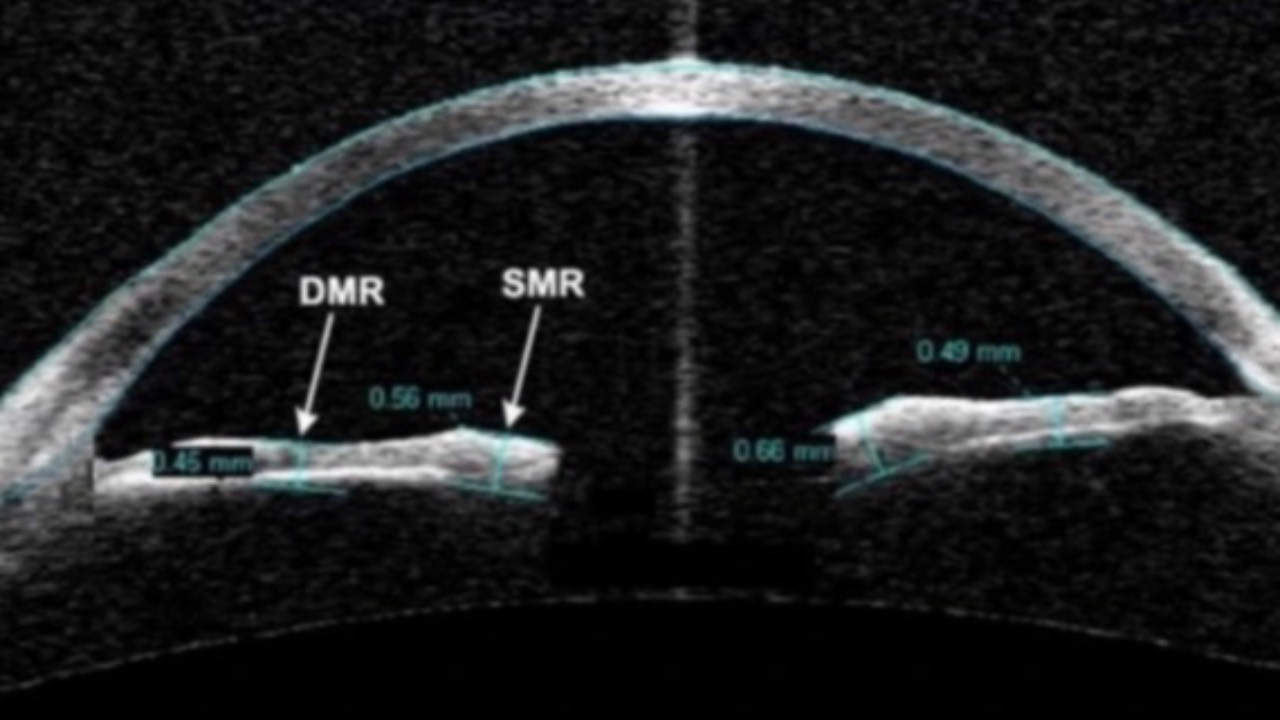

Home OCT?

A recent prospective trial published in Retina investigating home optical coherence tomography (OCT)-guided management of neovascular age-related macular degeneration (nAMD) has yielded promising results.

The study, involving 15 patients over 6 months, demonstrated a sig...